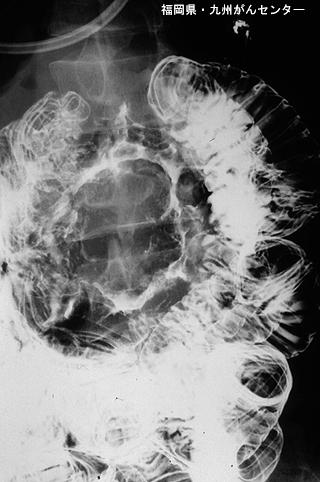

A case of a metastatic jejunal tumor originating from pulmonary giant cell carcinoma in a patient whose chief complaint was melena.

Fukuoka Pref., National Hospital Organization Kyushu Cancer Center

[ Image ID:4002 ]

Metastatic tumors/

Location

Small intestine/Ileum

Technique, Method

X-ray

40 -